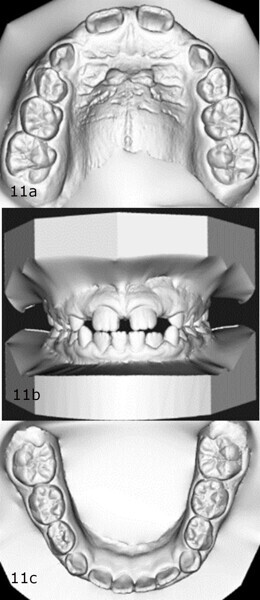

The 8-year-old male patient presented with a diastema between teeth #11 and 21 and non-eruption of teeth #12 and 22 (Fig. 1). The patient underwent a thorough orthodontic examination, including intra-oral photographs, extra-oral photographs, cephalometric radiography of the skull with cephalometric tracing, dental panoramic tomograms, impressions by intra-oral scanning, and functional and phonetic tests. Intra-oral examination (Fig. 2) and pattern analysis showed a Class I molar and canine relationship and contraction of the maxillary arch, displaced pre-contact between teeth #63 and 73, a 3.7 mm diastema between teeth #11 and 21, a mandibular midline deviation to the left, a maxillary midline to the right, and an open bite (−1.5 mm).

After 18 months of therapy, a case reassessment was carried out to verify that the goals had all been achieved (Fig. 8). Comparison of extra-oral photographs at the start of treatment (T0) and end of treatment (T1; Fig. 9) showed that excellent balance of the patient’s face had been achieved with a regular, symmetrical smile. Comparison of the intra-oral photographs (Fig. 10) and models (Fig. 11) also showed wider and more harmonious arch forms, closure of the anterior diastema, closure of the open bite and recentring of the mandibular midline. Excellent gingival trophism had also appeared.